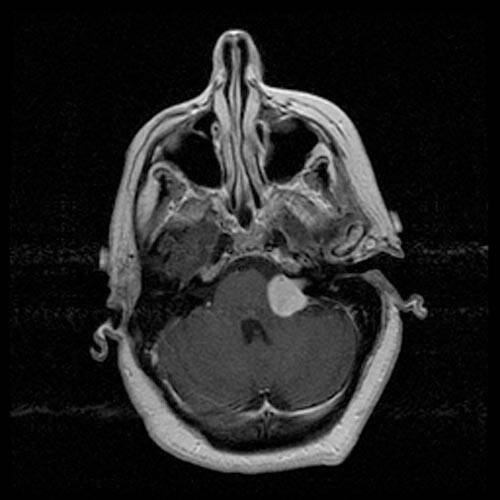

Brughoektumor (Vestibulair Schwannoom)

Een tumor van de omhulling (zenuwschede) van de gehoor- en/of de evenwichtszenuw heet een brughoektumor (vestibularis-schwannoom of acousticusneurinoom). Het is een goedaardige tumor die vernoemd is naar de plek in de schedel: de brughoek. De brughoek ligt achter in de schedel, in de schedelbasis en bevindt zich zowel links als rechts in de hoek tussen de kleine hersenen (het cerebellum) en een deel van de hersenstam; de pons.

Op de afbeelding is een eenzijdige brughoektumor te zien.

By RadsWiki - RadsWiki, CC BY-SA 3.0, https://commons.wikimedia.org/w/index.php?curid=3520114